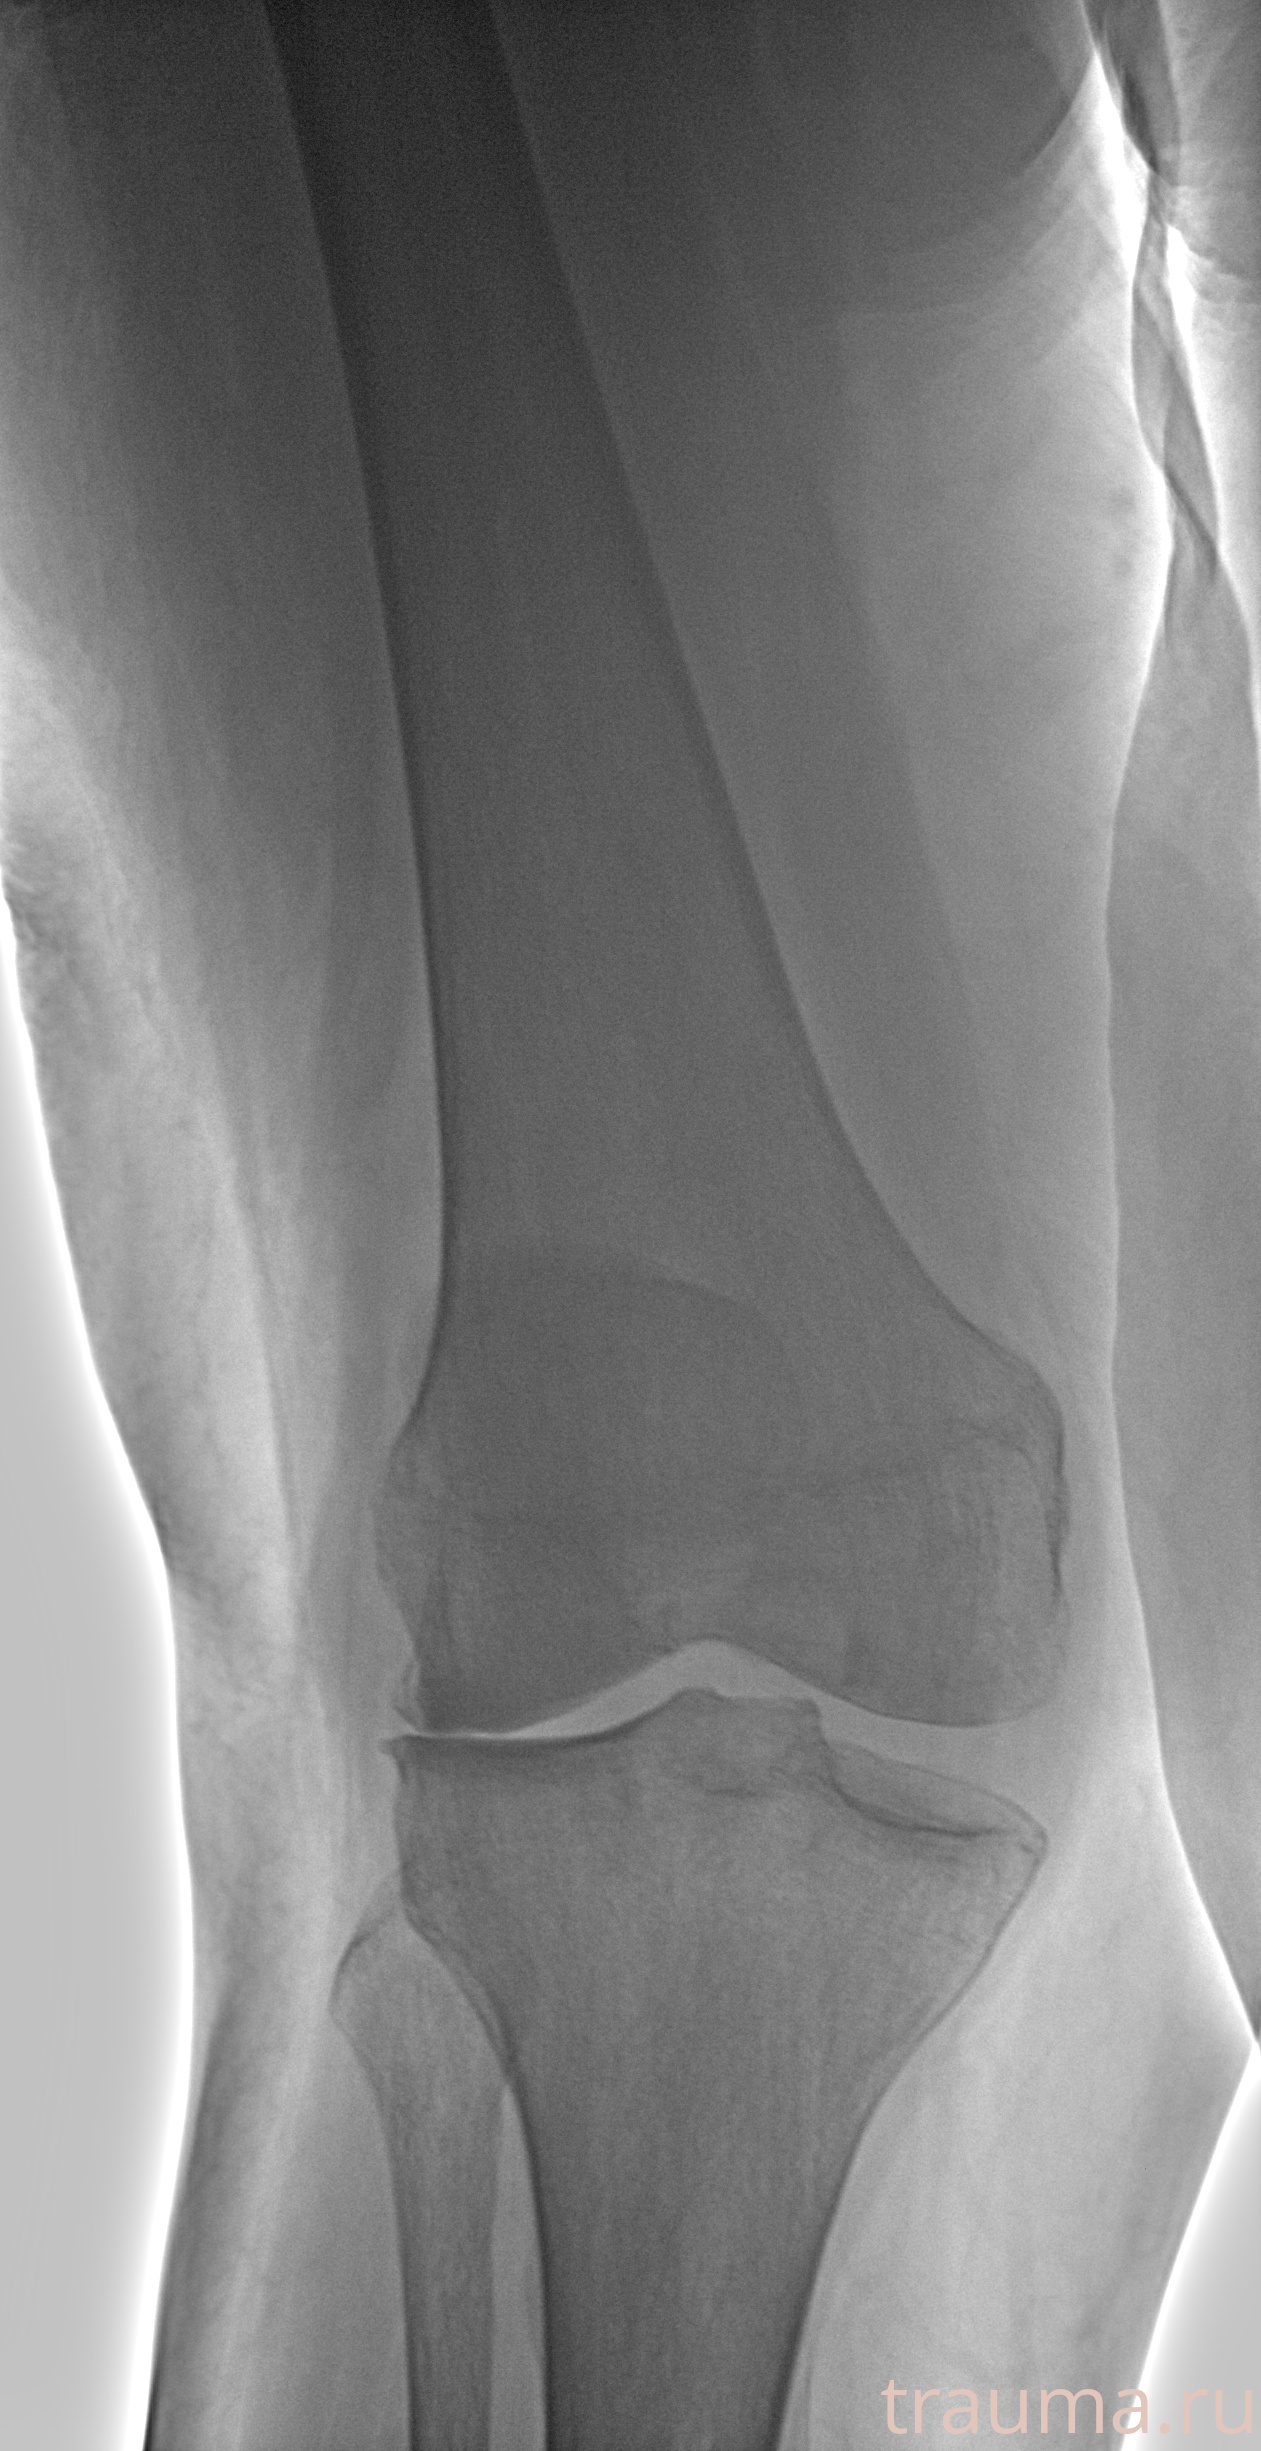

Рентген на дому: по вашему адресу приезжает врач-рентгенолог, травматолог-ортопед с мобильным рентгеновским аппаратом, проводит диагностику травмы или заболевания, делает необходимые рентгенограммы, дает рекомендации по дальнейшему лечению. Получить качественные снимки в домашних условиях возможно благодаря уникальной методике, разработанной МосРентген Центром для института  Склифосовского

при переломе шейки бедра и пневмонии от компании МосРентген Центр - партнера Института имени Склифосовского